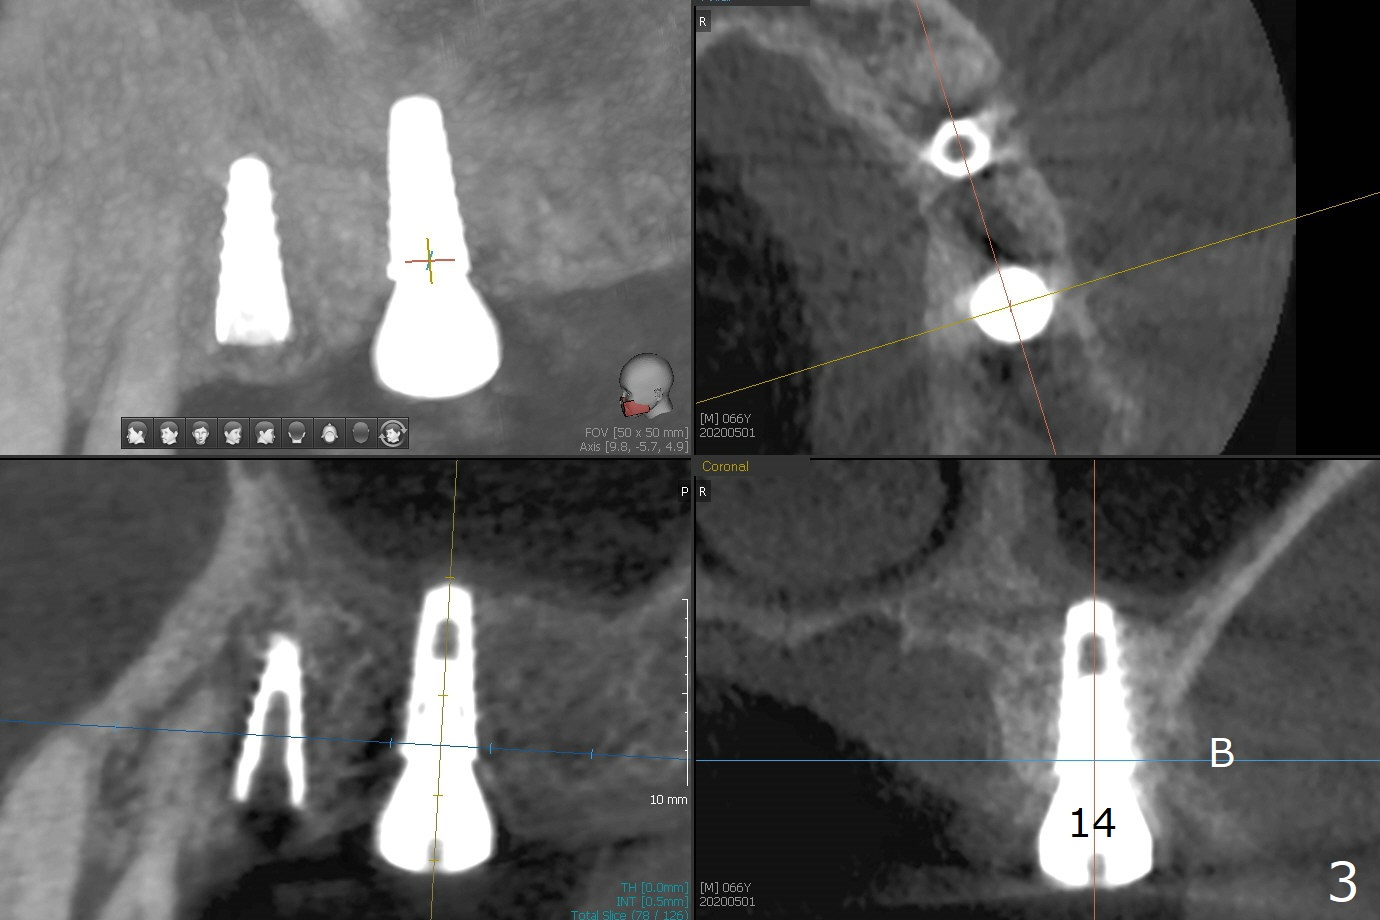

The patient returns for #4 extraction and immediate implant the 1st day clinic reopening after coronavirus lockdown. To reuse autogenous bone for #4 buccal gap closure, delayed implants are also placed at #13 and 14. It is much easier to determine the placement level of the immediate implant (open socket) with guide than that of the delayed ones (flapless) clinically. Immediate postop CT is taken for implant placement level confirmation (Fig.1-3). In fact the autogneous bone is too soft to be packed into #4 socket gaps. It has to be mixed with allograft to be packable. There is oozing when #14 healing abutment is placed. The hemorrhage is severe 4 days postop. The healing abutment is replaced by a healing screw. Hemostasis is achieved when the access is closed with GEM Cap and 4-0 Chromic gut suture. The patient will return for #3 extraction and socket preservation 1 month postop (Fig.4). To prevent postop hemorrhage, a cemented or temporary abutment will be placed at #4 before anesthesia, while .5 or 1.0 cc Augma bone will be placed at #3, covered with collagen plug and acrylic. In fact he cancels the appointment once because of symptom relief and will return 2 months postop. Sticky bone (Fig.5 *) and PRF is used at #3 for hemostasis, while a 5x5.7(3) mm pair (final) abutment is used to hold acrylic dressing in place. The latter remains in place with good oral hygiene 1 month postop (Fig.6 A: abutment). When the acrylic dressing is removed, the socket heals (Fig.7 K: the gingiva between the buccal and palatal sockets when the tooth was removed). The patient returns for impression 4.5 months postop. When the 5x5.7(3) mm abutment at #4 is reseated after cleaning, there is no horizontal gap between the abutment and implant in BW (Fig.8), while there is in PA (Fig.9). When a smaller abutment is seated (Fig.10), there appears to be a horizontal gap, whereas there is no vertical one. The situation is the same with #13 (Fig.11,12). The common denominator is 3.5 mm implant. With suspicion, BW is taken for the implant at #4 immediately before cementation (Fig.13). It appears that the abutment is most likely seated completely. There is no bone loss or screw loosening 4 months post cementation (Fig.14,15). One month later the patient agrees to have 3 lower implants to replace RPD.